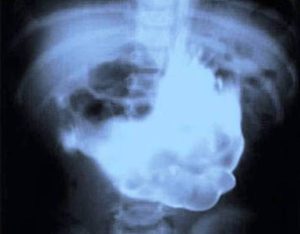

18. A Seven Inch Kidney Stone

This kidney stone seems so huge that it could not possibly be real. But it is. This kidney stone was found inside a patient in Hungary and it was a massive 7-inches long and wide. Thankfully, it was successfully removed which was a huge relief to the patient.Advertisement